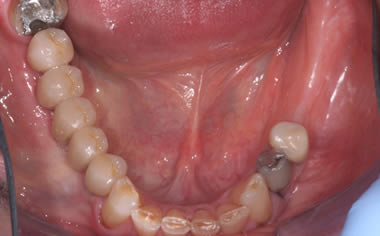

More back teeth replaced by dental implants

Case Five (4 images)